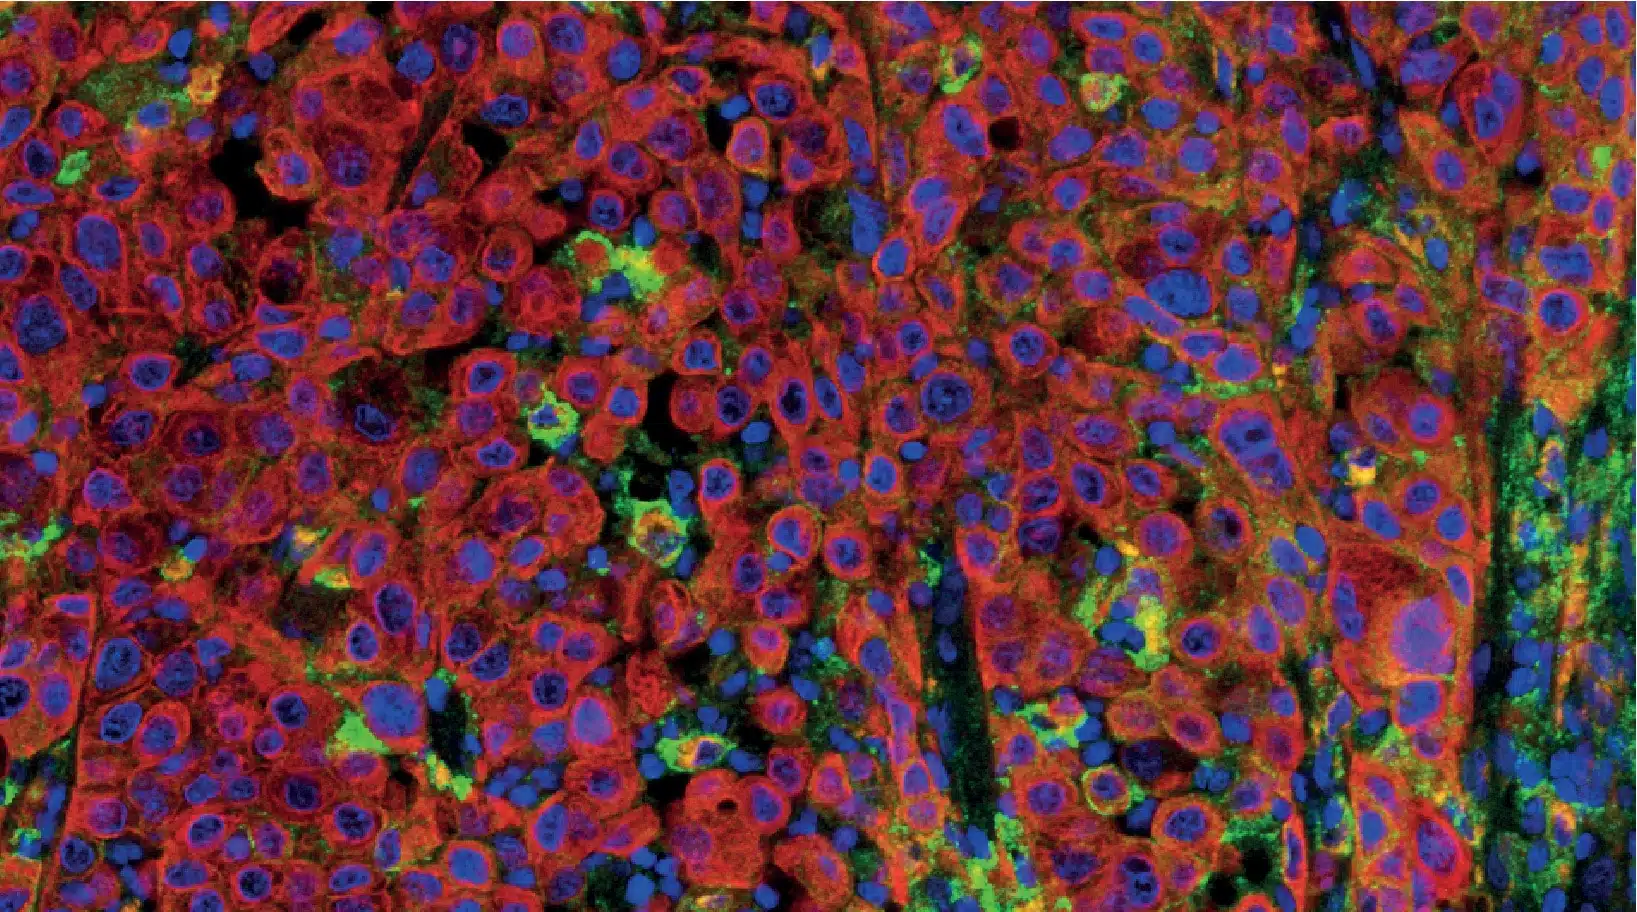

HBRI ヒストプロファイル® マルチプレックスIHCパネル

メラノーマ PD L1 クローン SP263 1

HBRIは、カスタムマルチプレックス開発と検証に加え、特定の表示に対してすでに検証済みのパネルも提供しています。

例としては:

• 組織内記憶 T細胞 CD8/CD49a/CD3/CD68/CD103

• デンドリチン細胞 ランゲリン/CD1a

• T細胞活性化 CD8/Ki-67/GranzymeB

• T-reg Light CD3/CD8/FoxP3

• PD-L1 CD68/panCK/PD-L1

• チェックポイント阻害剤 CD3/CD8/PD-1/PD-L1/カスタム

• 神経マクロファージ CD68/CD163/GFAP/TMEM-119/c-maf